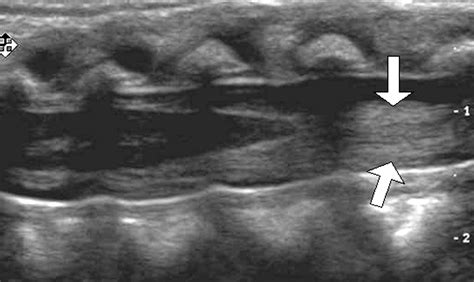

Dokter biasanya akan melakukan pemeriksaan fisik yang teliti untuk menguji refleks dan sensasi di area panggul. Namun, karena sifatnya yang darurat, langkah diagnostik utama dalam menangani Sindrom Conus Medullaris adalah pemeriksaan radiologi segera. Magnetic Resonance Imaging (MRI) adalah standar emas untuk memvisualisasikan kompresi saraf di area tersebut.

• MRI Tulang Belakang: Untuk melihat lokasi kompresi dengan detail yang akurat.

• CT Scan: Digunakan jika terdapat kontraindikasi terhadap MRI atau untuk melihat struktur tulang dengan lebih tajam.